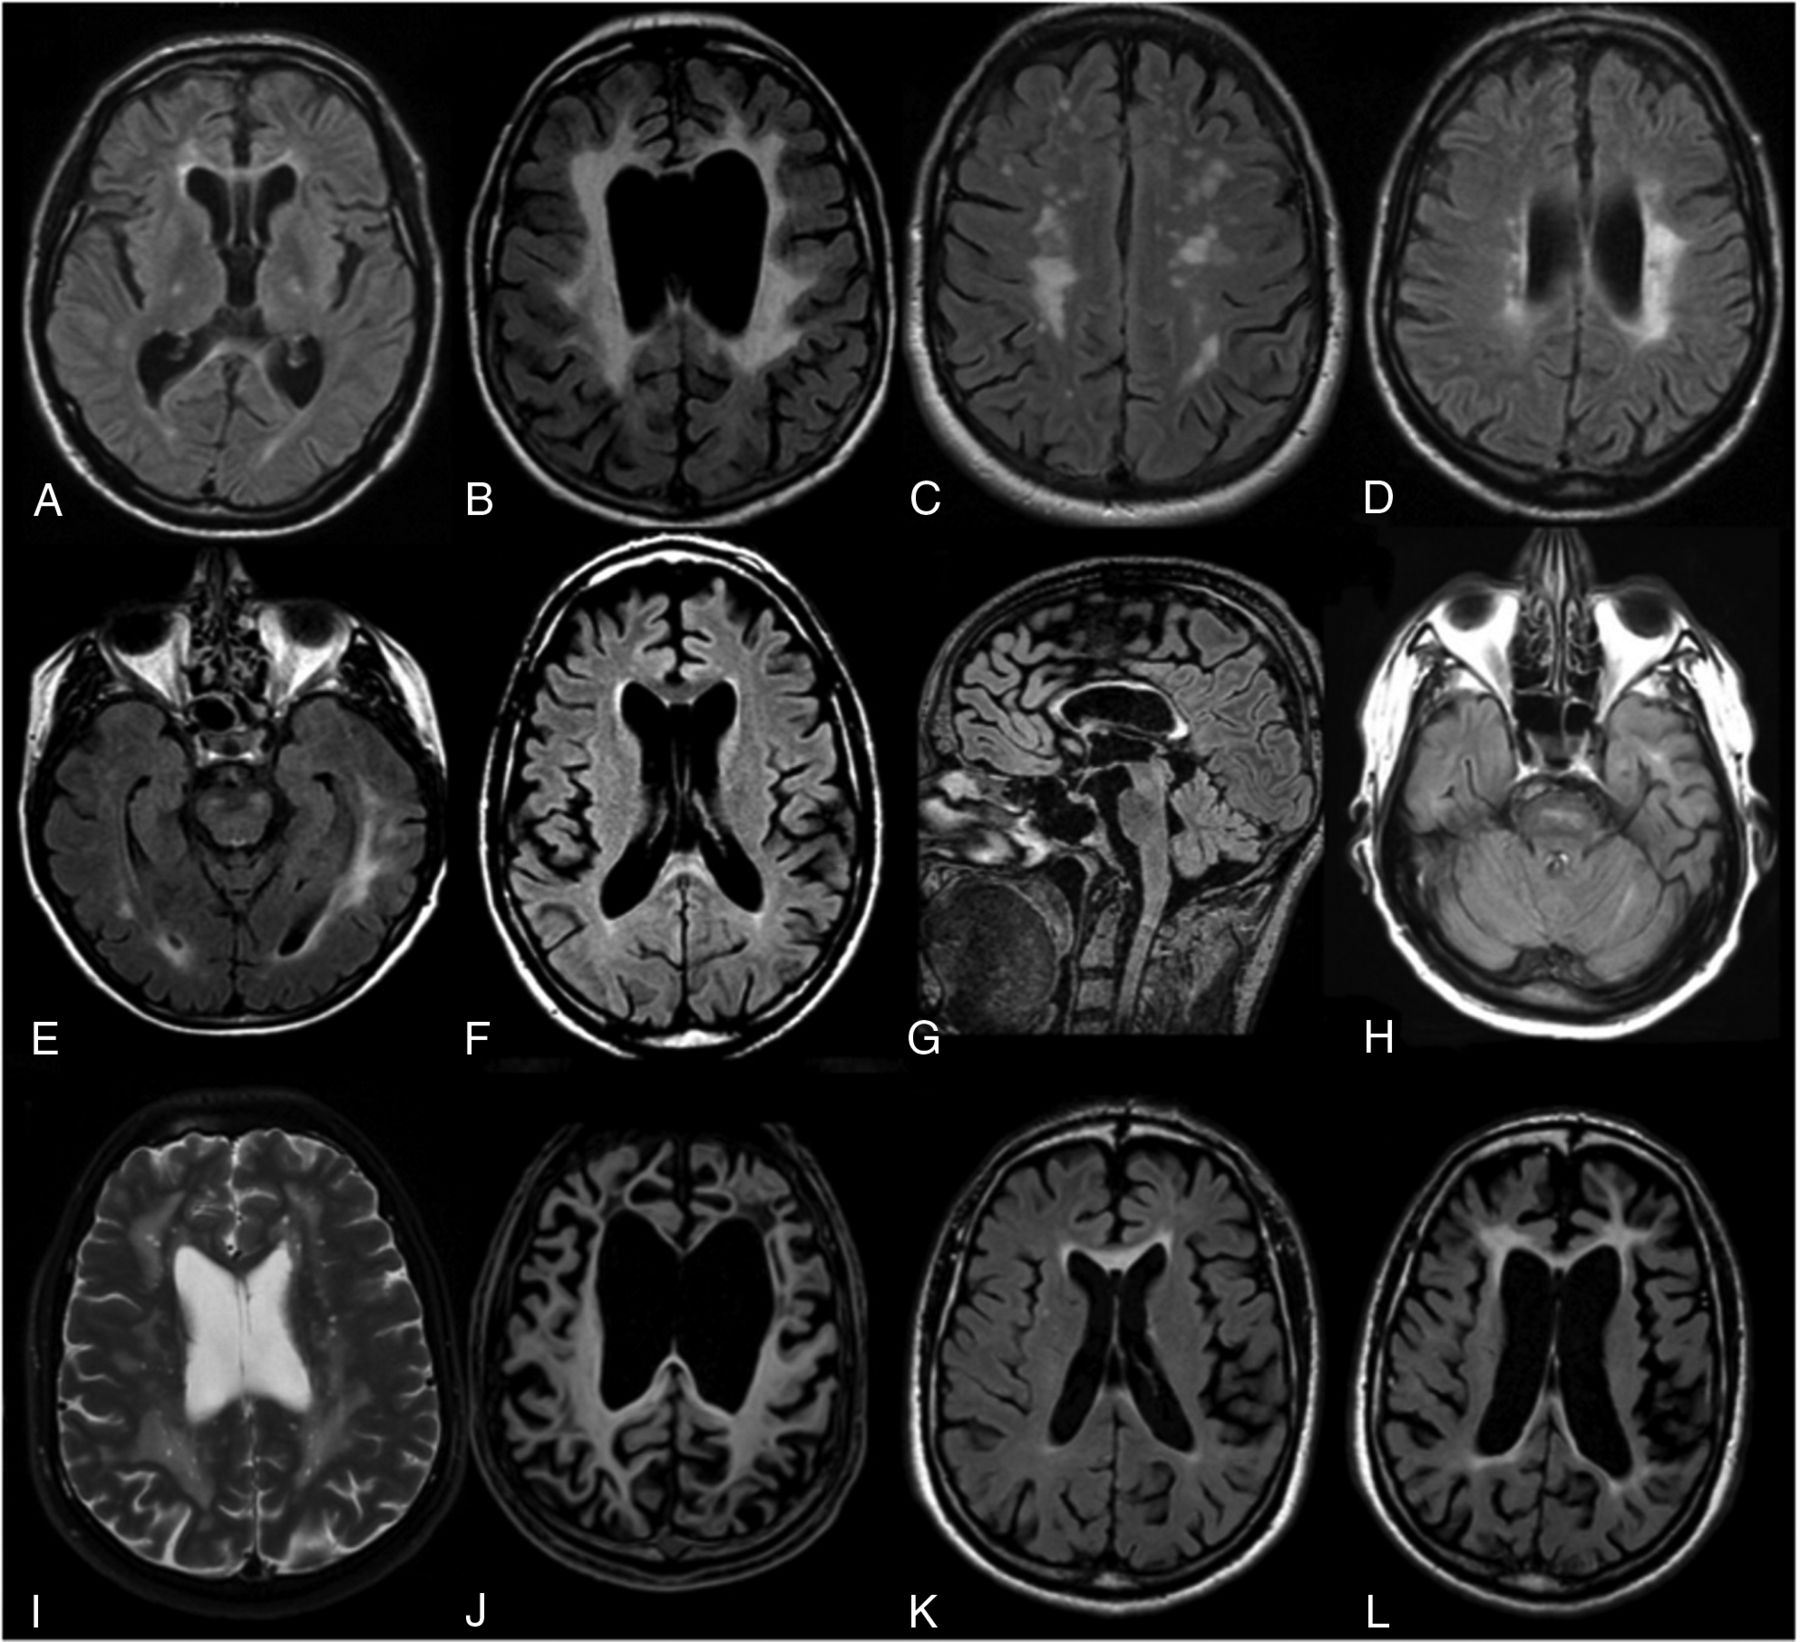

The mean delay between symptom onset and MR imaging was 2.0 years (range, 0.5–5 years). Bilateral, predominantly frontal and parietal T2/FLAIR white matter hyperintensities (WMH) associated with T1 hypointensities were present in all patients, even if they were subtle in some patients (Fig 1A and Table 2). Temporal and occipital abnormalities were observed in, respectively, 69% and 50% of the cases. WMH were confluent in 63% (Fig 1B) and patchy in 37% (Fig 1C), and a clear asymmetry was seen 37% of the patients (Fig 1D).

Characteristic MR imaging abnormalities in patients with ALSP on FLAIR (A–H, K, L), T2WI (I), and T1WI (J) images. MR imaging usually discloses subtle (A) or marked (B) white mater hyperintensities with frontal predilection (B). WMH can be confluent (B) or patchy (C) and are usually asymmetric (D). Corticospinal tract involvement (A and E) and corpus callosum involvement (F and G) are frequent. At the posterior fossa level, WMH can be of a vascular-like type (H). Some patients can present with enlarged perivascular spaces on T2WI (I). T1WI frequently reveals atrophy, usually marked, with frontal predominance (J). During a 32-month follow-up (case 8), a clear increase of WMH and atrophy is seen (K and L). A cavum septum pellucidum is frequently observed (A and B).

Pyramidal tract hyperintensities were noted in 63% of the patients (Fig 1A, -E), with an involvement of the internal capsules in 10 and of the brain stem in 3. Three patients had spinal cord MR imaging; findings were always normal. Corpus callosum abnormalities were almost always present with hyperintensities in 81% (Fig 1F) and atrophy in 88% of cases (Fig 1G). Deep gray matter nuclei and external capsules were involved in, respectively, 13% and 44% of patients. Posterior fossa hyperintensities were seen in 37% of the patients: Half of these patients had pontine vascular-like lesions (Fig 1H). The cerebellum was always spared. Enlarged perivascular spaces were seen in 25% of patients (Fig 1I).

Brain atrophy was almost constant (94%), and 4 patients had marked atrophy (Fig 1J). It was usually more pronounced in patients with diffuse WMH and predominated in the frontal (40%) or frontoparietal (53%) areas.

None of the 6 patients with contrast MR imaging showed gadolinium enhancement. Ventricular abnormalities, including cavum septum pellucidum and/or cavum vergae (Fig 1A, -B), were seen in 50% of the patients. Five patients (cases 7, 8, 11, 14, and 15) had an MR imaging follow-up after a mean of 15.3 months (range, 5–32 months): Supratentorial WMH worsened in all patients (Fig 1K, -L), usually associated with marked brain volume loss.